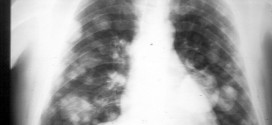

CÁNCER DE PULMÓN

Cáncer de pulmón. Otros tipos u nombres: neoplasia pulmonar,  neoplasias pleurales primarias, tumores hiliares, tumores en lóbulo medio o lóbulo inferior derecho, neoplasia microcítico pulmonar, neoplasia pulmonar central, neoplasias torácicas, etc. Los pulmones son un par de órganos que dan oxígeno al cuerpo y expulsan el dióxido de carbono, un producto de desecho producido por las células del cuerpo. Los …